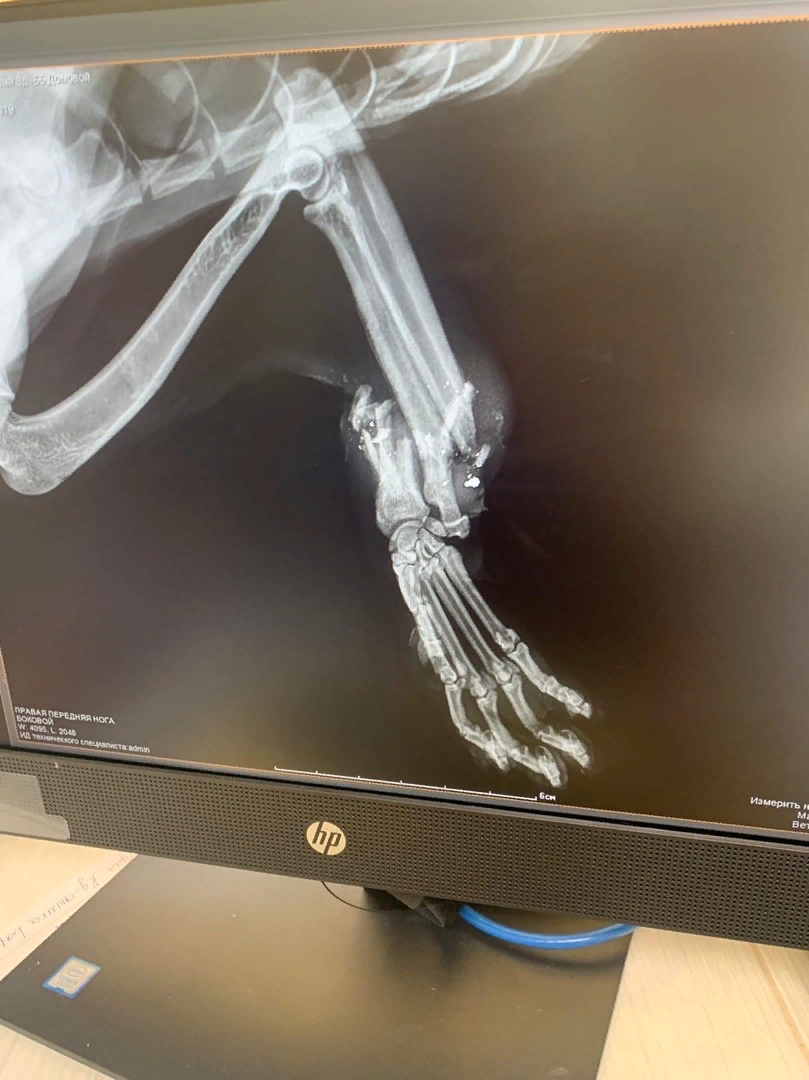

Котик молил о помощи! Лапка была как тряпочка, его заметили волонтеры и отвезли в клинику. Там выяснилось, что у кота - огнестрельное ранение - раздроблена лапа. Сейчас котика уже прооперировали, лапку удалось спасти! Назвали Домовой.